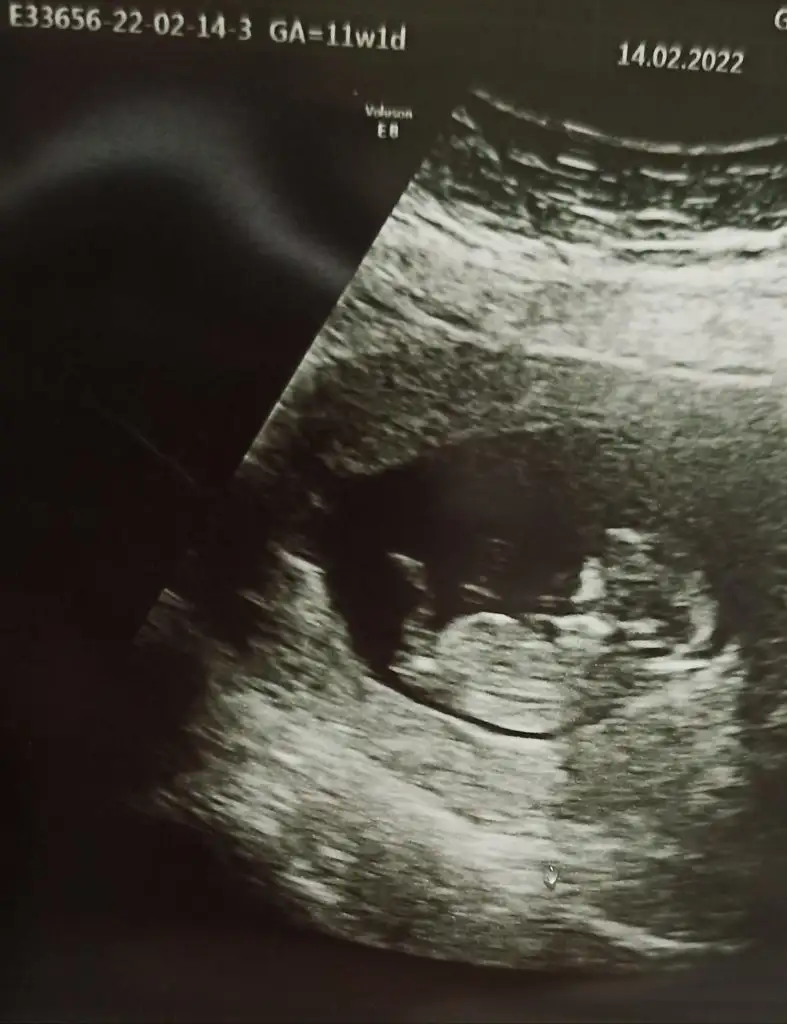

Maşallah erkek benceÇok hareketliydi ya sırtını falan döndü bi ara ekliyorum usg görüntüsü tahminleri bekliyorum

Yaa yüzü çok tatlı duruyor maşallah erkek benceÇok hareketliydi ya sırtını falan döndü bi ara ekliyorum usg görüntüsü tahminleri bekliyorum

Sağlıkla gelsin bakalım kimlerim tahmini tutacakYaa yüzü çok tatlı duruyor maşallah erkek bence

Ya maşallah, bence tombik bir kız buKizlar benim bebişimi tahmin edermisiniz çatlicam yakinda14 martta doktor randevum daha çok var